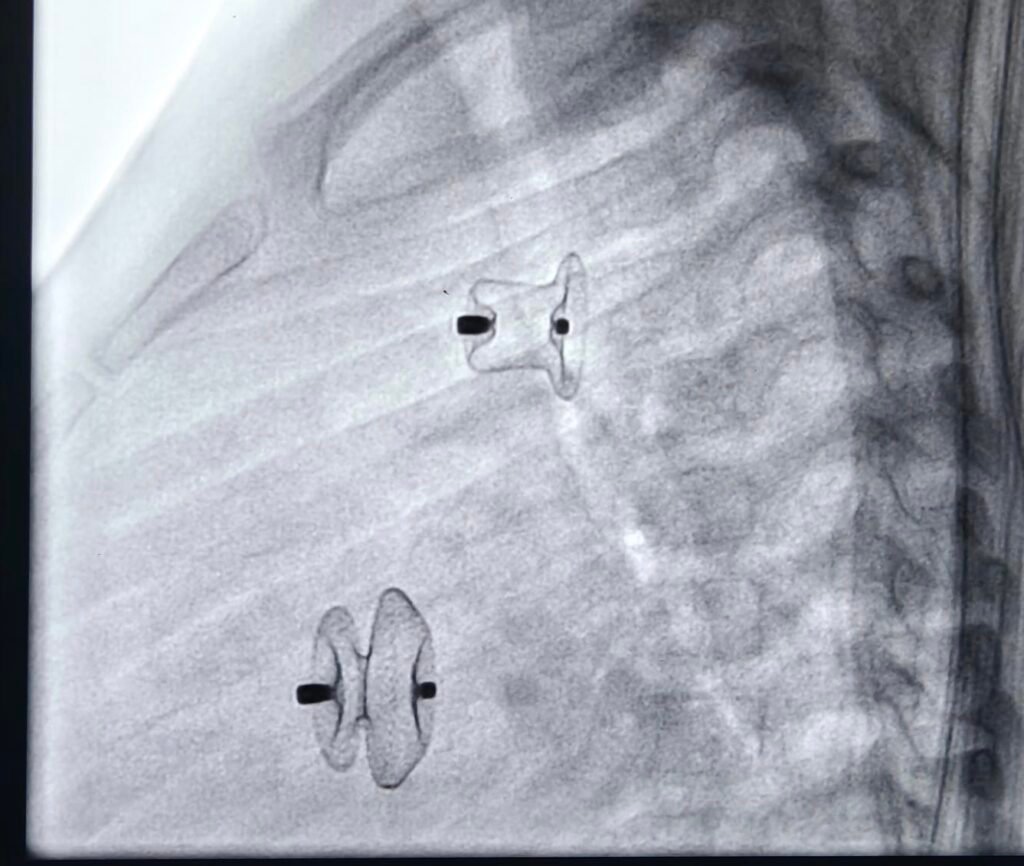

VSD Device Closure

Pioneering VSD device closure in coastal Andhra Pradesh. Successfully did a VSD device closure at Medicover hospitals, MVP colony, Visakhapatnam. Thanks to Dr Surendhra , Praveen senior cath technician, sarala sister and the entire team for the support. I thank almighty for his blessings